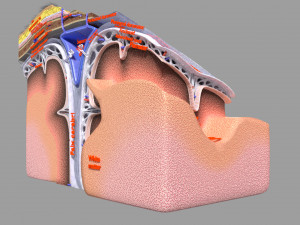

Brain with meninges scalp detailed labelled 3D 3D मॉडल

A blend model of brain along with its covering layers (meninges), skull bone and scalp labelled in detail and anatomically precise. The parts depicted are white, gray, pia, arachnoid, dura, bone, skin, fat, aponeurosis, periosteum, falx cerebri and more.

The material is high resolution image textures and normal maps based on non overlapping UVs. The texture and normal maps are packed with the blend file itself.